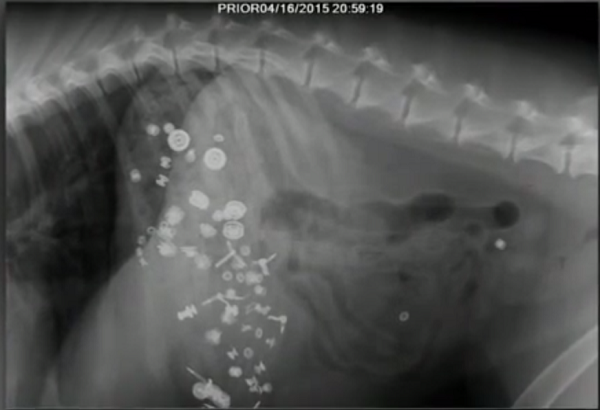

透過x光檢查,清清楚楚發現摩卡胃裡散落著齒輪、彈簧跟金屬碎片,也幸好傑夫動作快,這些金屬物沒有釀成大禍,由獸醫師手術取出。